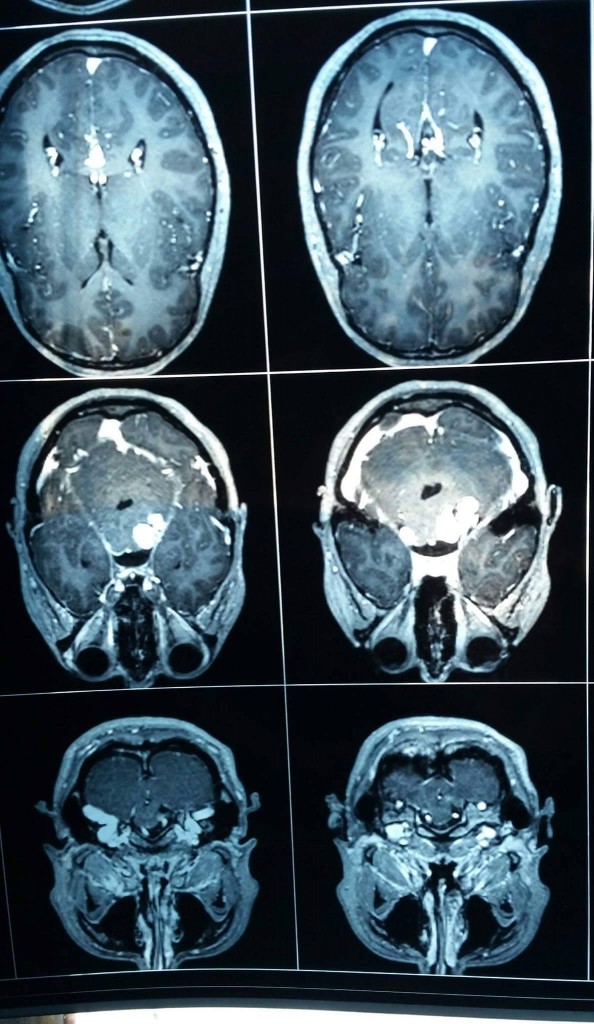

Acum mai bine de un an a intrat in echipa Ada (Adriana Iliescu), 23 de ani. O stiam de ceva vreme pentru ca evolua intr-o alta echipa de mixt asa incat s-a integrat cat ai spune “goool”. O tipa extrem de talentata, foarte muncitoare, cu zambetul pe buze. Insa de ceva vreme zambetul a inceput sa ii dispara, locul acestuia fiind luat de ingrijorare. Am aflat de curand ca motivele de ingrijorare ale Adei sunt mai serioase decat am fi dorit. Diagnostic: neurofibromatoza de tip 2 cu neurinom acustic bilateral compresiv pe trunchiul cerebral, maningioame ale fosetei Meckel dreapta si cervical cu compresie medulara.

Neurinoamele acustice sunt afecţiuni benigne destul de rar întâlnite, insa nemiloase. Pierderea auzului este numai primul pas, urmand o data cu marirea lor si risc de pareza, paralizie si alte complicatii.